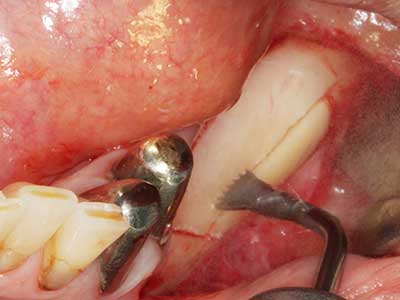

Fig. 27: 21-year-old patient after conversion osteotomy with persistent retrognathy with class II dysgnathy.

Fig. 28: During removal of metal, the basal chin regions are separated with the Piezomed while retaining the lingual blood supply.

Fig. 29: Forward displacement of the chin by 5 mm and fixation with two osteosynthesis plates (KLS Martin). The two mental nerves can be detected in the marginal region.

Fig. 30: The aesthetic improvement in the chin contour after the operation can be clearly seen.